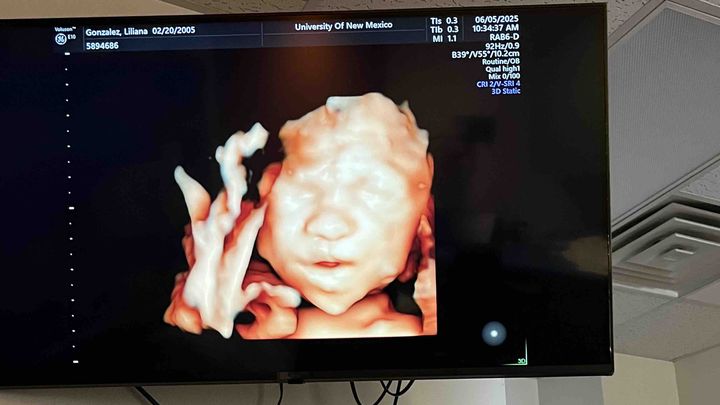

Hi my name is Lilliana Gonzalez I’m 25 weeks pregnant and I’m having to make travel plans to Denver, Colorado or California for my unborn baby he has a heart defect called pulmonary atresia

and I’m having to travel to a specialist and I’m trying to raise money to help get us there. Anything is gladly appreciated!